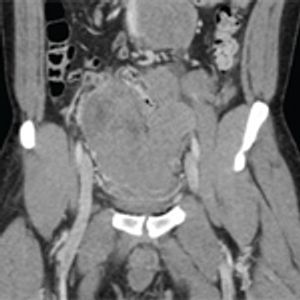

A 35-year-old man with a known history of tuberous sclerosis complex was referred to the urology clinic by his primary care physician for consultation regarding bilateral, multifocal renal masses.